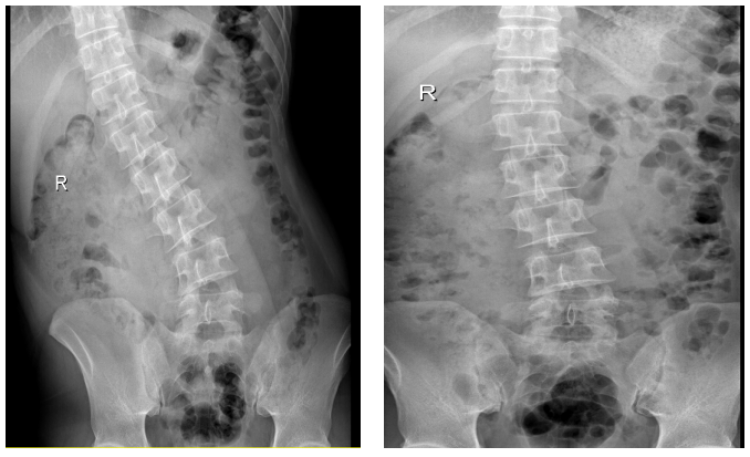

△术前术后腰椎侧弯程度DR对比

廖先生来到上海德济医院骨科进行详细检查,廖先生再次确诊是腰椎间盘突出症,继发腰椎侧弯。